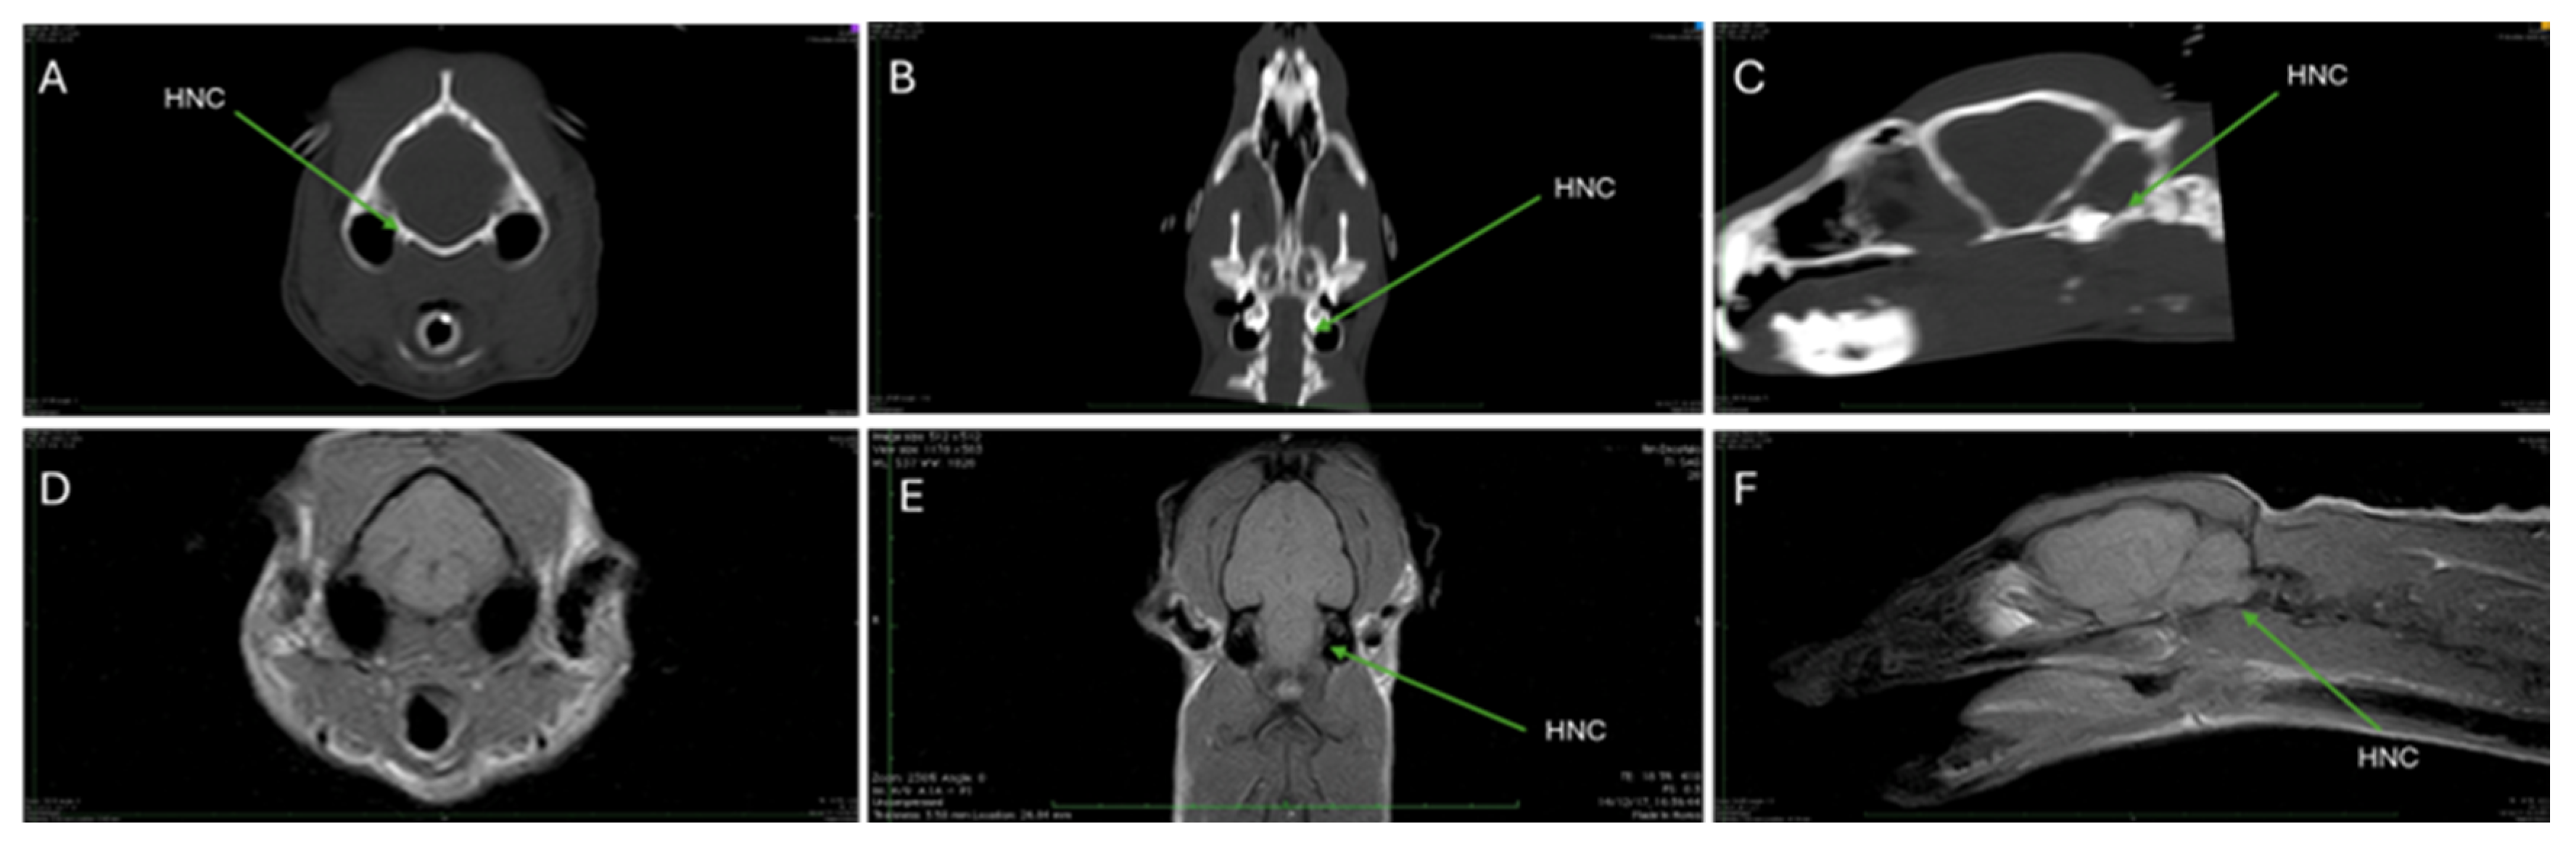

| HNC | Hypoglossal nerve canal |

3.3. Magnetic Resonance Imaging (MRI)